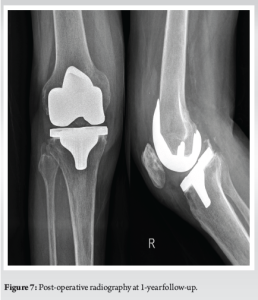

A 77-year-old male with right knee pain was diagnosed with advanced OA. In pursuit of relief, the patient underwent GAE at another hospital. Following the procedure, the patient developed swelling, increased pain, and skin discoloration, necessitating readmission to the same hospital for vascular observation and pain control. Redness, swelling, and pain subsided over a period of 7 days, and the patient was discharged from the hospital (Fig. 1). After a 6-month recovery period, owing to persistent osteoarthritic knee pain, the patient sought further treatment options at our hospital. Upon consultation with our radiologists, an arteriogram was performed 1 year after embolization, and it was ascertained that the genicular arteries remained patent (Fig. 2). Consequently, a decision was made to proceed with total knee arthroplasty to manage OA. During arthroplasty, bone samples of bone cuts from the weight-bearing distal femur and proximal tibia were sent for histopathological examination, and the results were negative for osteonecrosis (Fig. 3). The post-operative period involved meticulous monitoring of complications such as wound dehiscence, tissue necrosis, and infection. Fortunately, aside from the mild erythema observed around the knee a week after the procedure, which did not require any treatment, the wound healed well without any complications, with standard rehabilitation of same-day walking, and ROM exercise could be initiated (Fig. 4 and 5). After 1 year of follow-up, the patient experienced relief of knee pain and achieved a knee range of motion of up to 0°–120° and back to his day-to-day activities, indicating a successful outcome following total knee arthroplasty (Fig. 6 and 7).